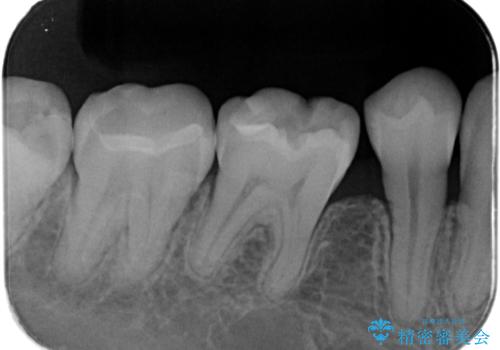

左下7番咬合面にコンポジットレジン修復されてり、経年劣化による着色や歯質との境目にう蝕を認め、セラミックインレーでのやり替えとなりました。

左下7番咬合面にコンポジットレジン修復されてり、経年劣化による着色や歯質との境目にう蝕を認めました。

コンポジットレジンとセラミックの物性的特徴を説明し、セラミックインレーでのやり替えとなりました。